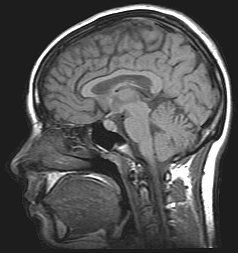

MRI

MRI of the human brain.

It is usually desirable to study memory in humans because we have the ability to subjectively describe experiences, and have the intellect to perform complex and indirect tests of memory. Lesion studies allow us to reduce the neural mechanisms of memory, and results from finely constructed psychological tests can help us make inferences about how memory works. Neuropsychologists attempt to show that specific behavioural deficits are associated with specific sites of brain damage. The famous case of HM, a man who had both his medial temporal lobes removed resulting in profound amnesia, illustrates how brain damage can tell us a lot about the inner workings of memory. One of the fundamental problems with studying human patients who have already acquired brain damage is the lack of experimental control.[1] Comparisons usually have to be made between individuals; exact lesion location and individual differences cannot be controlled for.